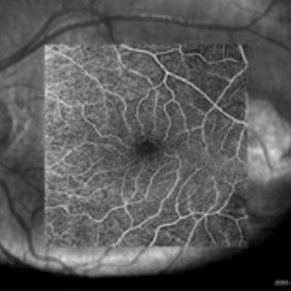

Deep capillary plexus OCT-angiography of an asymptomatic 12-year-old girl with torpedo maculopathy of the left eye. No abnormality.

Photographer: Pierre-Henry Gabrielle, Ophthalmology department, Dijon University Hospital, France

Imaging device: Zeiss Cirrus OCT

Condition/keywords: optical coherence tomography (OCT), torpedo maculopathy